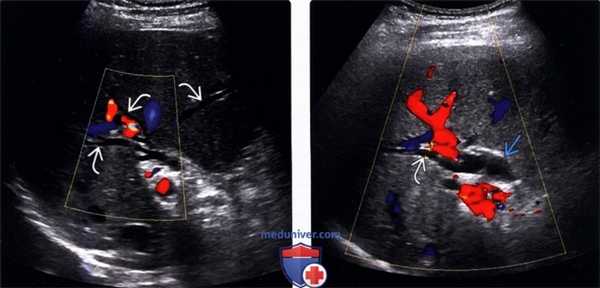

• Цветовая допплерография:

о Позволяют достоверно дифференцировать расширенные протоки (в которых отсутствуют признаки кровотока) от прилегающих сосудистых ветвей печеночной артерии и воротной вены

(Левый) При цветовой допплерографии на поперечном УЗ срезе печени наблюдается легкое расширение внутрипеченочных желчных протоков их диаметр немного превышает два миллиметра. Причиной легкой дилатации желчных протоков стала обтурация конкрементом (не показан).

(Правый) При цветовой допплерографии на поперечном УЗ срезе печени наблюдается небольшое расширение внутрипеченочных и внепеченочных протоков. У пациента был диагностирован стеноз ампулы в сочетании с холангитом, которые стали причиной дилатации желчных протоков.